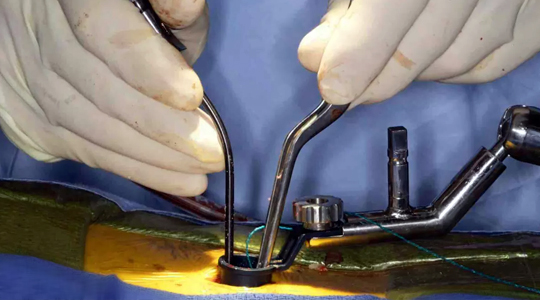

Posterior Fusion

Posterior fusion with instrumentation is the most common operation done for idiopathic scoliosis. In posterior fusion the spine is operated on from behind with an incision straight down the back. Various types of rods, hooks, wires or screws are used to partially straighten the spine and hold it fast while the bone fusion occurs.

These surgeries are performed under intraoperative neuro-monitoring system which gives continuous input to the surgeon about the function of the spinal cord throughout the surgery. This enables safe application of screws into the spine, bony correction and straightening of the deformed spine without risks of injuring the spinal cord.